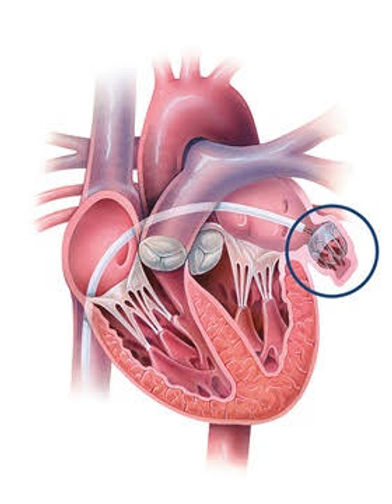

“Antikoagülan ilaç kullanma zorunluluğunu ortadan kaldıran ve her geçen dakika hızla yayılım gösteren Watchman, hastaların yaşam kalitesini yüksek oranda arttırmaktadır.”Dünyada kalp krizi ve kanserden sonra en sık karşılaşılan ölüm nedenleri arasında bulunan inmenin en büyük kaynağı olan atriyal fibrilasyon (AF), dünyada %1-2 arasında bir görülme oranına sahiptir ve yaş ilerledikçe görülme sıklığı artmaktadır. Hatta 80’li yaşlarda bu oran %15’e kadar yükselmektedir. Hastaneye yatırılan her beş inmeli hastadan birinde sebep olarak AF gösterilirken bu hastaların morbidite oranının diğer inme nedenli hastalardan daha fazla olduğu acı sonuçlarla ortaya konmuştur.Oral antikoagülan (OAK) ilaç kullanımı atriyal fibrilasyonda ciddi önem arz etmektedir. Bu tedavi yöntemi sayesinde AF ile inme riskinde %70, ölüm oranında ise %25 azalma sağlandığı gözlemlenmiştir fakat OAK tedavisi; çok sayıda besin ve ilaçla etkileşim göstermesi, sık doz ayarlaması, transfüzyon gerekliliği ve dar bir terapötik aralığa sahip olması gibi birçok problemi de bünyesinde taşır. Hastaların yaşadığı bu sorunlardan kaynaklı olarak atriyal fibrilasyon tedavisinde yeni arayışlara gidilmiş ve çalışmalar, inmede trombüsün en ciddi kaynağı olarak bilinen sol atriyal apandisite yönelmiştir. OAK tedavisinde kontrendikasyonu olan hastalarda sol atriyal apandisin (SAA) kapatılması, inmenin önlenebilmesi için alternatif bir tedavi seçeneği olarak geliştirilmiştir. Cerrahi ve perkütan yolla uygulanabilen bu tedavide cerrahi uygulamanın başarı oranı düşüktür. Cerrahi yöntemler, yalnızca atriyal fibrilasyonu olan ve kalp ameliyatı geçirmiş hastalara önerilmektedir. Perkütan yolla yapılan SAA kapanmasında ise son yılların göz bebeği olan ve Amerika Gıda ve İlaç Dairesi (FDA) tarafından onaylı “Watchman cihazı” kullanılmaya başlanmıştır (3).

Watchman, kalbin atriyal yüzünü kaplayan bir kumaştan ve kendinden genleşebilen sabitleme pervaneli nitinol çerçeve yapısından oluşur. Nitinol çerçevede yer alan küçük kancalar, cihazın SAA duvarına tutunmasını sağlar. Watchman’in SAA ostiyum çapından daha büyük olması gerekir, bu yüzden farklı vakalar için cihazın 21-33 mm arasında beş farklı boyutu geliştirilmiştir (2).

Cihazın implant prosedürü genellikle bir saat sürer ve hasta o günü hastanede geçirir. Hastaya genel anestezi altında transseptal tekniği kullanılarak kateterizasyon uygulaması gerçekleştirilir ve hangi boyutta Watchman cihazının yerleştirileceğini belirlemek için hastanın sol atriyal uzantısı ölçülür. Bunun için ise ekokardiyografi ve bu yöntemin yetersiz kaldığı durumlarda transözofageal ekokardiyogram (TEE) kullanılır. Bu gerekliliğe yol açan durumlar; kalpte pıhtı veya enfeksiyon varlığının araştırılması, yapay kapak işlevlerinin değerlendirilmesi, kalp kapak tamiri veya kalp kapaklarının kapatılması ameliyatları sırasında ve sonrasında ameliyatın başarı durumunu ölçmektir.Doğru boyutlarda cihaz seçildikten sonra Watchman kılıfı, femoral venden girilerek tel üzerinden sol atriyuma ilerletilir. Erişim kılıfı pigtail kateter üzerinden SAA’nın distal kısmına gönderilir. Dağıtım sistemi hazırlanıp erişim kılıfına yerleştirildikten sonra Watchman de SAA’ya yerleştirilir. Cihaz uygulamaya geçmeden önce son kez floroskopi ve TEE ile kontrol edilir. Son olarak cihaz açılır, böylece SAA kapanır ve hastalar operasyon sonunda antikoagülan almayı durdurup inme riskini azaltmış olurlar (1).